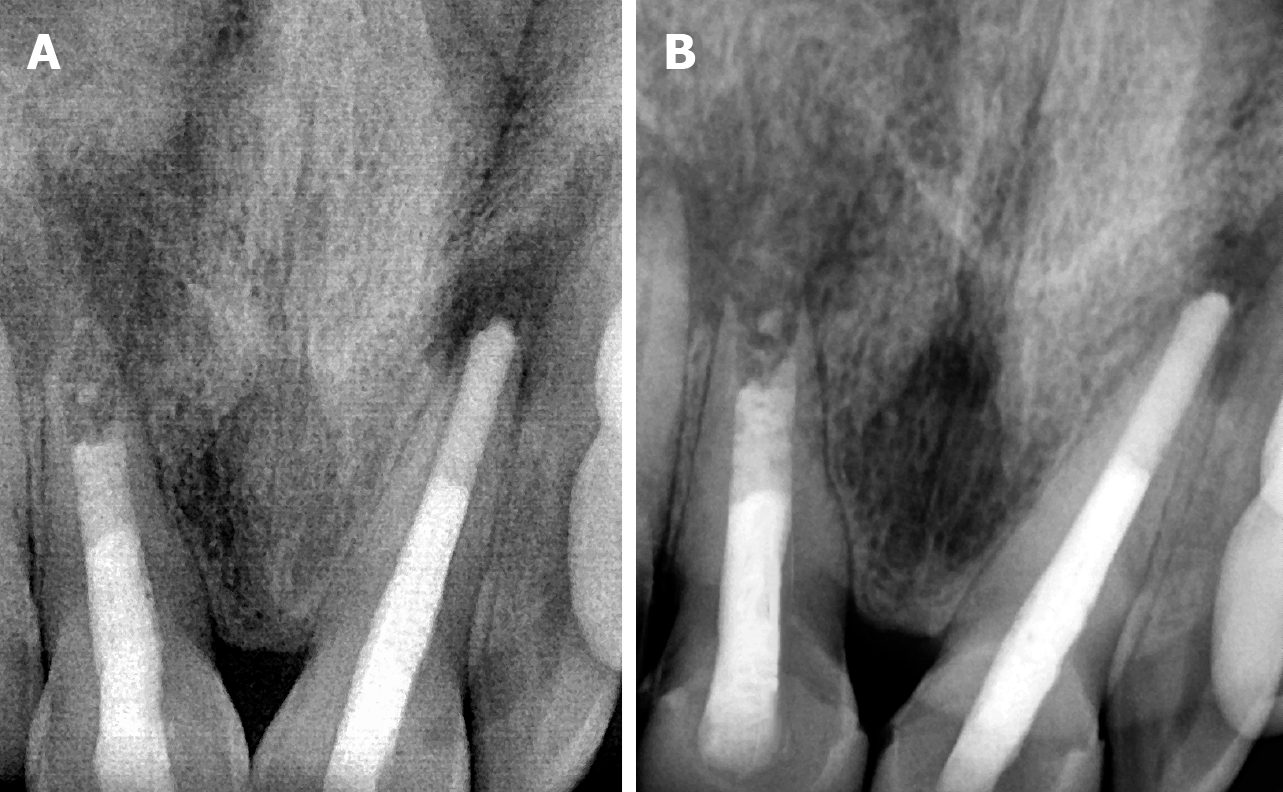

Figure 12 Shows the radiograph showing follow-up.

A: 3-month follow-up; B: 6-month follow-up.